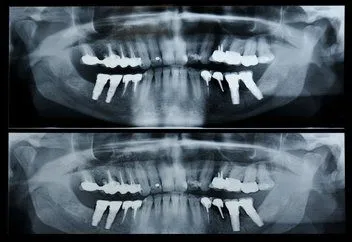

Panorex

Pan_x_ray.jpg A panorex is a very impressive piece of imaging machinery in that it is capable of identifying many issues and structures that a normal x-ray is not. Initially you will sit in a chair with your chin on a small ledge. Once positioned in the machine, it will rotate around your entire head taking a full 360 degree view of the teeth, head, sinuses and bones.

The ability to view the full structure of your head as a whole is very informative to the dentist. It will allow us to see any potential problems and make sure that everything is functioning as it should be. The panorex is capable of viewing specific types of structural problems, infections or asymmetry among many others.